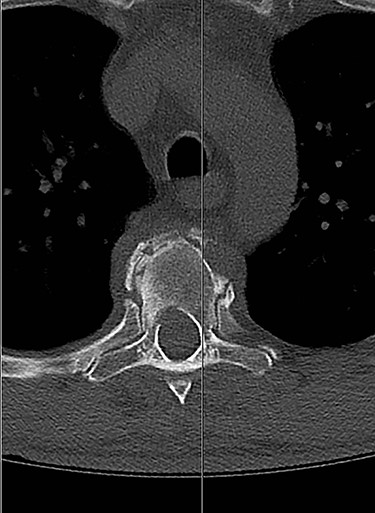

Spinal images are presented in Figs 1–6. Cross-sectional imaging revealed no other neoplastic lesion. He received dexamethasone 10 mg bolus then 4mg four times daily with appropriate proton pump inhibitor coverage. Due to no distinguishable major arterial feeder upon review of the imaging jointly with the neuroradiologist, pre-operative embolization was not attempted. The following morning, he underwent posterolateral right costotransversectomy, ligation of the ipsilateral T4 nerve root, T4 vertebrectomy and insertion of an expandable titanium cage with T1–T7 pedicle screw fixation (Figs 7 and 8). Post-operatively his pain improved to VAS 2/10 and motor power in his left lower limb improved to MRC grade 4/5. The patient was discharged home Day 10 post-admission with physiotherapy.

Post-operative, sagittal CT images of the T1–T7 pedicle screw fixation and expandable titanium cage in situ.